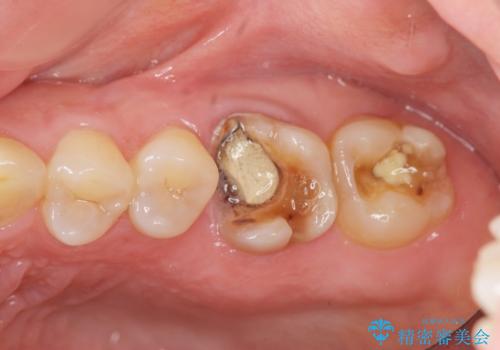

- 銀歯が取れたのち放置してしまいセラミック治療を希望され来院されました。

虫歯の再発も見られたので、丁寧に虫歯を取り除いたのち根管治療を行いジルコニアクラウン・セラミックインレーにより修復処置を行いました。